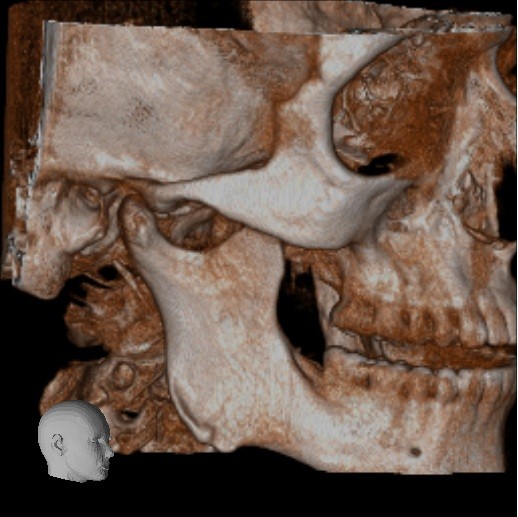

Below are some screenshots from my Cone Beam CT scan and the report linking possible ES. I have more Regular CT scans I could possibly share and/or if you would like me to get possible better angles from the Cone Beam CT scan let me know. But as of right now I’m at a loss as what to do going forward. I do have an MRI with and without contrast of the Cervical Spine Scheduled, but that’s due to the doctor’s (the doctor that dismissed it as ES and one doctor that wants to follow up and learn more on it) wanting it.

- Now onto this year, I finally got better back to full health in late November early December 2024 and sadly started to get another sinus infect in January and still no answers to why. I just happen to be watching YouTube when a Dentist had said that your teeth could be linked to sinus issues causing sinus infections and normally the only way to tell if this is the case is to get a Cone Beam CT scan. I then thought this could be another lead to find out why I keep getting sick as I did when I was 10 have my first top premolar on my left side removed against what I wanted as they said my teeth were too crowded and it needed to be removed so I could have braces (which that dentist didn’t even do my braces anyway). But I thought when he removed it if a small piece of the root was still in there as he just broke out the tooth without removing it via surgical means that that could cause an abscess in my Left Maxillary Sinus where infections always start. So, finally I was able to find a place that would give me a Cone Beam CT scan back in February of this year all while I was just starting to get sick from my infection. Anyway, I finally got the report in March and found out oddly my Left side is mostly normal other than mucus polyps, but I have a few other issues (I have attached the report below). This report is where I first found out about Eagle Syndrome as it states I might have Calcified Ligaments and further testing is needed to confirm. It was only after this report and looking up what Eagle Syndrome was that I can say I have almost every symptom that has ever been reported. Sadly, I couldn’t find anyone in my State at the time that work with Eagle Syndrome and when I did was about a week before I found this site and the doctor I did see seemed to dismiss me as another hypochondriac and you can’t have it as you don’t have Vertigo type Dizziness, my styloid are normal length and I don’t have neck pain equivalent to having to be in a neck brace. Not only this she only looked at my CT scan from a week earlier that I had got in Emergency. The Emergency visit was due to the fact at 8PM that night I had pain in my Right Mastoid Bone, and I was starting to get an earache. I went to lay down and took pain meds and an ice pack in hopes to reduce the pain and swelling. I couldn’t sleep due to the pain and came upfront about 10PM. 10:21PM I couldn’t take it anymore and started to stretch my neck and I felt a huge snap and heard a load pop, all the pain just felt like it disappeared. One minute later, I had a massive pain that spread just like when you get an IV that stings, but it felt like someone was trying to murder me and stabbed a knife into the right side of my skull. I was in so much pain that I was hunched over, and we had to have an ambulance called. I thought I was having an aneurism and my mother thought I was having a Stroke (very rare ES Symptom). When the ambulance arrived, they took my vitals, and my blood pressure was 148/110 with a pulse in the high 90’s low 100’s. Luckily the pain had subsided enough that we were able to go to emergency without the ambulance ride, but while I was in emergency the pain had spread to my left side of my head and now felt like someone had taken a clothes iron and stuck it on my head. Any breeze moving my hair was pure agony and I couldn’t lay my head on a pillow without that burning pain. According to emergency though I must have just had a Mastoid Process infection and it burst. Luckily the pain went away by the time I went to the Doctor for ES, but like I said before they were of no help.